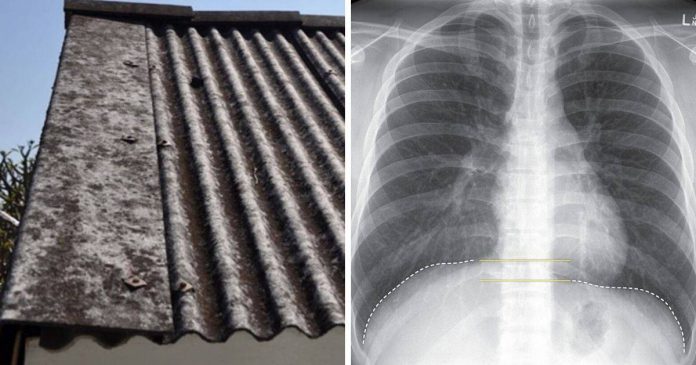

Kebanyakan rumah dan kilang menggunakan bumbung atap asbestos kerana ianya lebih murah dan memberi kesan penyejukan.

Namun begitu, selepas kajian menemui asbestos merupakan punca penyebab kanser mesothelioma, penggunaannya telah dihentikan dan dihadkan.

Menurut page Public Health Malaysia, sekiranya bahan merbahaya ini tidak diusik, risiko untuk mendapat kanser adalah sangat rendah. Risiko akan hadir apabila ianya pecah, rosak dan korang akan terlibat secara langsung dalam mengendalikan asbestos.

Situasi ini mendedahkan individu kepada risiko untuk mendapat radang asbestosis paru-paru dan juga kanser mesothelioma. Tidak perlu banyak, sebutir debu sehalus bilah jarum sudah cukup untuk korang mendapat kanser dalam tempoh 30 tahun akan datang.